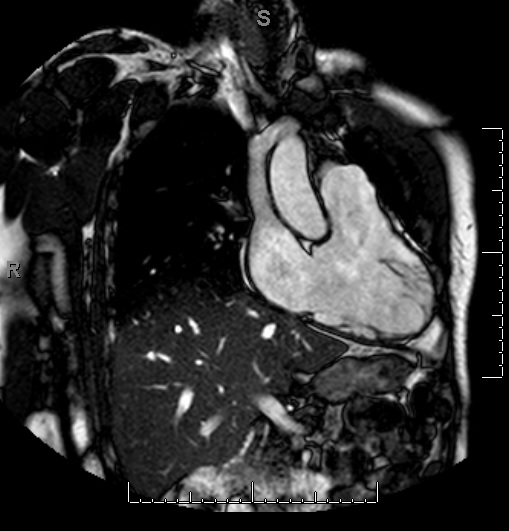

The echocardiogram demonstrates a small left-to-right atrial level shunt, dilated right ventricle, severe pulmonary valve insufficiency, and moderate tricuspid insufficiency. Exercise stress test reveals mild, non-specific ST-T changes with maximal workload of 13.7 METS.

Figure 1

Quantification of right ventricular (RV) size and function cannot be accurately assessed by echocardiography. Cardiac MRI is now considered the gold standard for RV evaluation.1,2 The RV end-diastolic and systolic volumes can be accurately measured as well as the RV ejection fraction and pulmonary valve regurgitant volume and fraction. RV volumes indexed to body surface area have become the accepted criteria used to determine operative timing, though the threshold varies by institution. In addition, decreased RV function, particularly in patients followed with serial MRI imaging, is considered an indication for intervention. ECG (QRS duration >180 ms) and Holter monitoring can reveal pathologic arrhythmias (ventricular tachycardia, atrial fibrillation and IART/flutter) that in and of themselves are an indication to intervene.3,4

Based on the patient's RV dilation, he was indicated for pulmonary valve replacement in addition to closure of the atrial septal level shunt. The pulmonary valve was replaced with a 29 mm porcine prosthesis. Intracardiac examination of the atrial septum identified a stretched patent foramen ovale, which was closed primarily. The tricuspid annulus was found to be dilated, and in the setting of moderate-to-severe regurgitation on preoperative transesophageal echocardiogram, a tricuspid valuloplasty (34 mm annuloplasty band) was performed. Postoperative demonstrated no pulmonary valve insufficiency, bilateral pulmonary venous return, normal RV function, trivial tricuspid insufficiency and no residual atrial level shunt. He had an uneventful recovery. After surgical follow-up is complete, he is scheduled for routine follow-up with a cardiologist with expertise with adult congenital heart disease in addition to his primary care physician.5